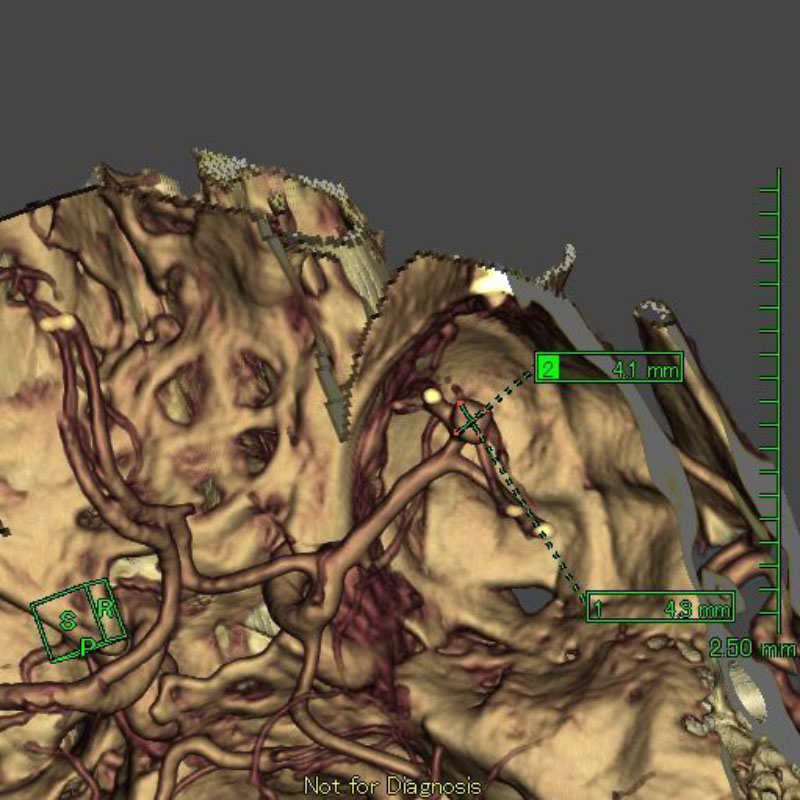

手術前

クリップ前

クリップ後

手術後